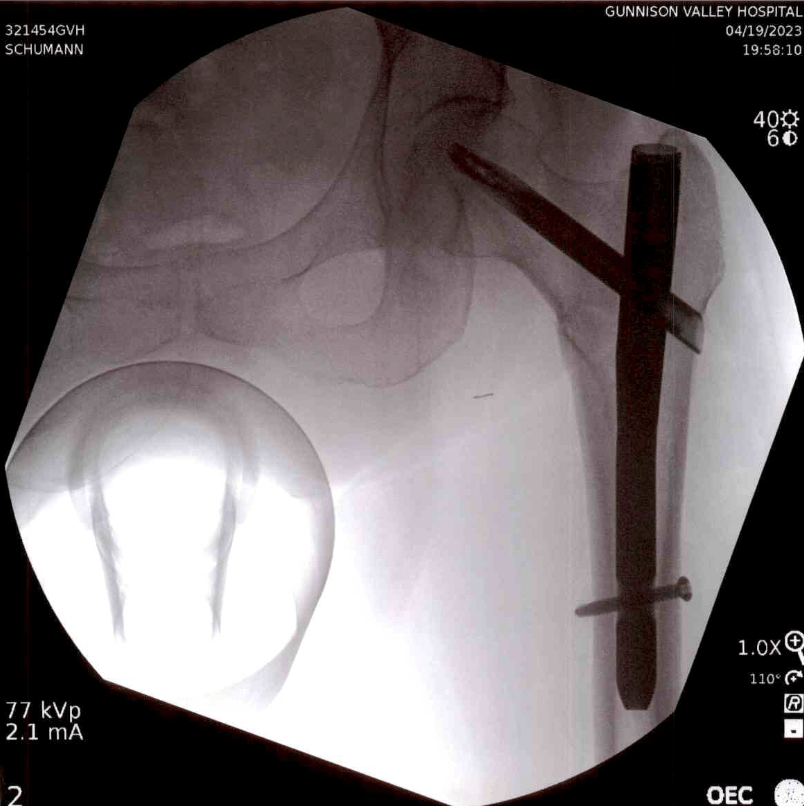

“Hip” turns out to be kind of a nebulous concept, and really what Lynn did was fracture (in closed fashion) her intertrochanteric femur. So I keep saying hip because I think it conveys the drama better, while Lynn keeps telling people she broke her leg, which may be more accurate but probably leads people to think of a calf-high walking cast. It’s a serious break, whatever you want to call it, and although she could have been fully weight-bearing if she wanted (she didn’t, and doesn’t, yet) the day after surgery, the knitting could take up to a year, or more.

Lynn, hopped up on fentanyl, acetaminophen, bupivacaine, lidocaine, ketamine and whatever else on her five-page hospital bill of nearly $68,000 (excluding the multitude of doctors) is pain med, wasn’t too worried about any of this, but I was a nervous wreck — and the delay, delay, delay of surgery wasn’t helping me, especially since I was never let anywhere near the surgical center. Once they got around to inserting a $6,000 nail into her femur, it only took an hour and went very well.